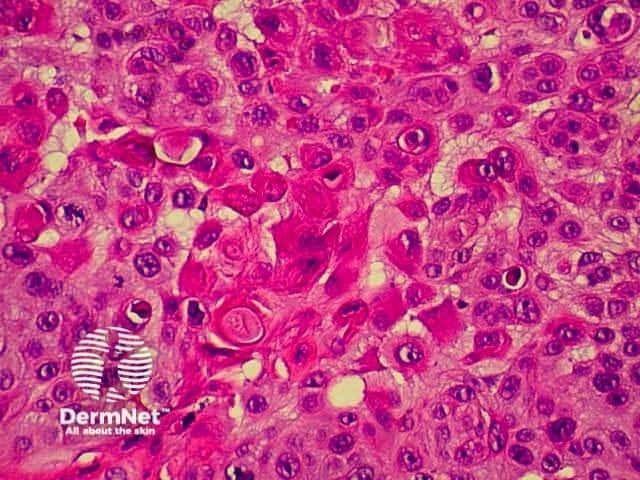

Invasive squamous cell carcinoma (SCC) is characterised by dermal invasion. Link to a clinical description of invasive squamous cell carcinoma.

SCC is characterised by proliferation of irregular nests of abnormal squamous cells arising from the epidermis and invading the dermis. Tumours are traditionally divided into well, moderately or poorly differentiated tumours by a subjective assessment of how significantly the tumour cells differ from normal keratinocytes. In general, the greater the degree of keratinization, the better differentiated the tumour is thought to be. Except in the case of very poorly differentiated tumours, this does not have a great bearing on prognosis. More important is the depth and irregularity of invasion, particularly the presence of perineural infiltration, which is associated with a much higher rate of recurrence if not widely excised. The site of the lesion is also important; tumours of the lips and ears have a considerably higher rate of metastasis to lymph nodes.

There are several descriptive variants of SCC including spindle cell SCC and acantholytic (or adenoid or pseudoglandular SCC). These mainly are of note due to the difficulty of diagnosing the tumour as SCC, but they may also imply a slightly worse prognosis. A further rare variant is verrucous carcinoma, a lesion in which the histology has a deceptively benign appearance in that there is very little cytological abnormality. Diagnosis in these cases may be delayed and the diagnosis may not be made until several biopsies have been performed. These tumours recur locally, but do not generally metastasise.

From the above comments it can be seen that the histological features of SCCs can vary, but in general are:

Pathology of SCC Pathology of SCC Pathology of SCC Pathology of SCC